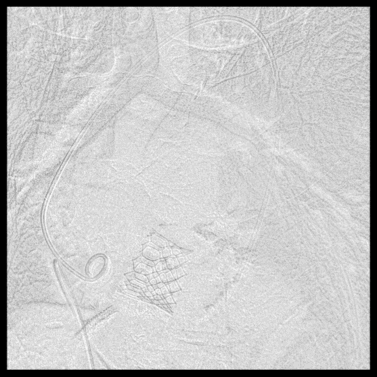

后续TAVR步骤与常规经股动脉TAVR类似:依次行主动脉根部造影、导丝跨主动脉瓣并交换猪尾导管、经左股静脉置入临时起搏电极、主动脉瓣球囊预扩张、在快速起搏下植入经导管主动脉瓣。

主动脉根部造影